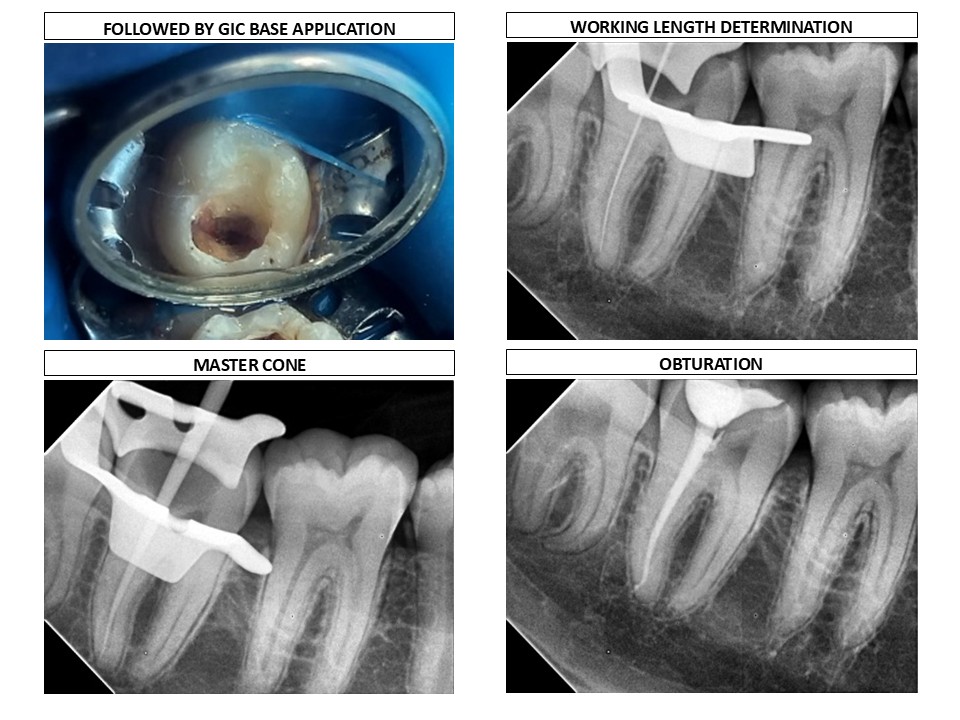

A total of 139 students competed in the south zone in the biodentine case competition for dental students. Dr Joselin Rosary is one among 139 participants to secure this coveted prize, due to the ingenuity of the endo vital therapy she performed in the Outpatient department of Madha Dental College.